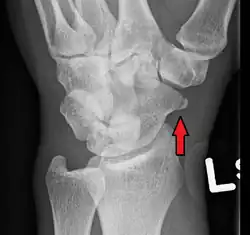

An X-ray showing a fracture through the waist of the scaphoid